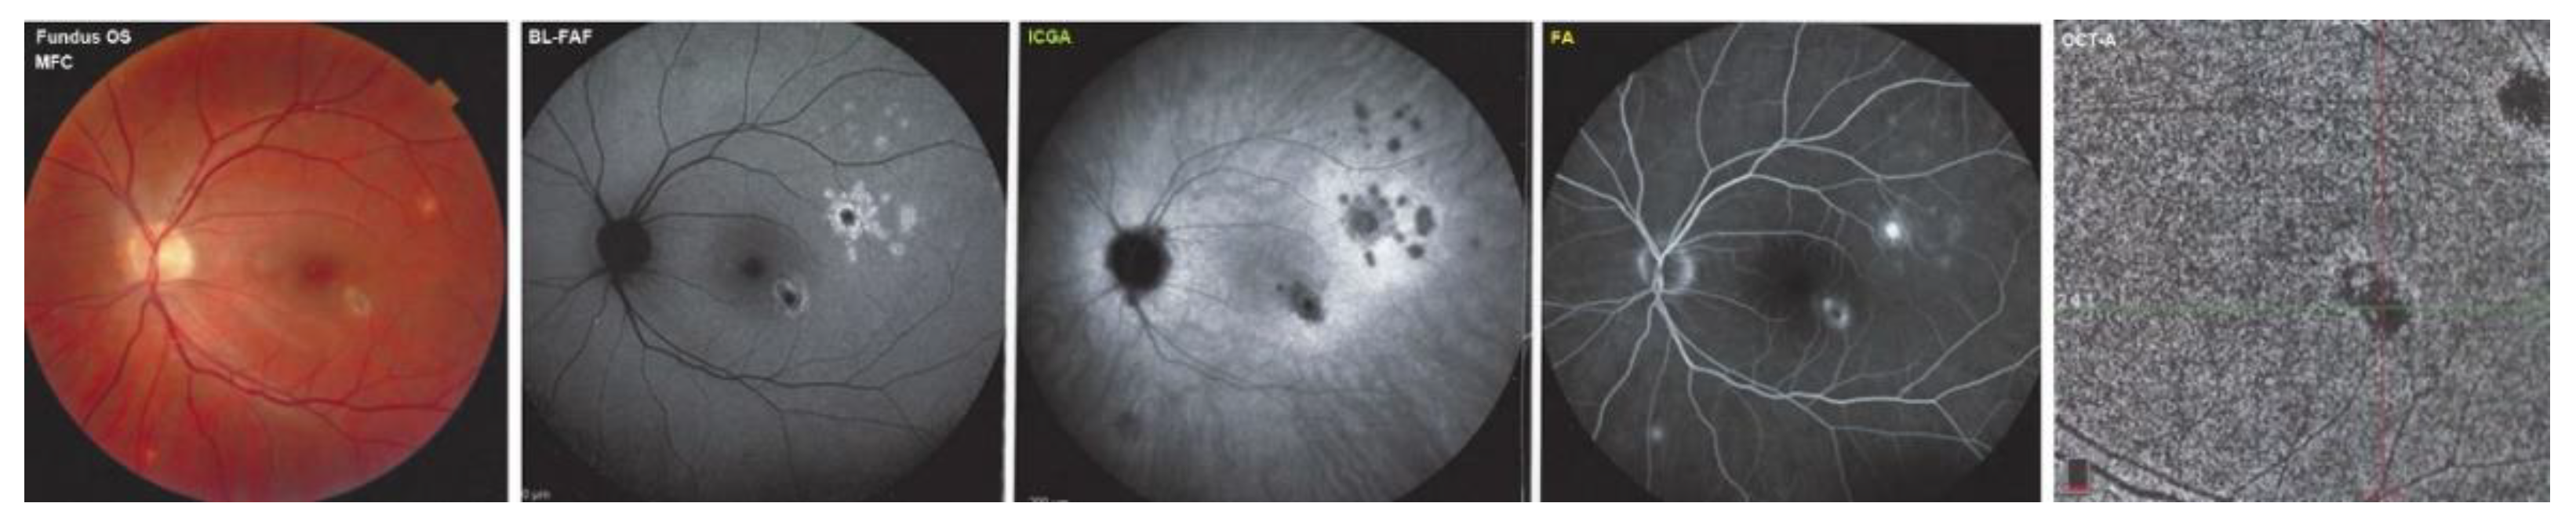

| Fundus | BL-FAF | ICGA | SD-OCT | FA | OCT-A | |

| MEWDS (n = 5) | Foveal granularity 4/5 | Positive-hyperauto-FAF 5/5 | Positive-hypofluo 5/5 | Damage/loss of IS/OS 5/5 | no/faint hyperfluor 1/5 | negative 2/2 |

| White dots 1/5 | moderate hyperfluor 4/5 | |||||

| MFC (n = 3) | Punched-out small scars | Positive-hyperauto-FAF 3/3 | Positive-hypofluo 3/3 | Damage/loss of IS/OS 3/3 | no/faint hyperfluor 3/3 | negative 3/3 |